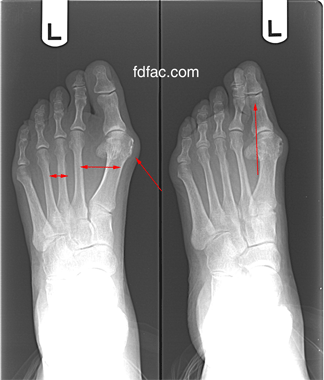

Reader Pete asks “I have been in a spin class for 8 months. Recently I have developed chronic right arch foot pain to the point that it’s difficult to walk for several days after class. I have severe flat feet that pronate inward-no arch at all. I am cycling with cage on pedal. Would cleats be better for the foot pain? The problem is worse when standing or climbing.”

Sounds like you’re getting plantar fasciitis (arch or heel pain). Your flat feet are most likely the cause. As long As long as you have stiff soled cycling shoes, it shouldn’t matter whether you use cages or cleats. As for the pronation, you might want to try a non-custom orthotic and see if this helps. Superfeet are good, and they make a cycling specific insoles (new yellow below).